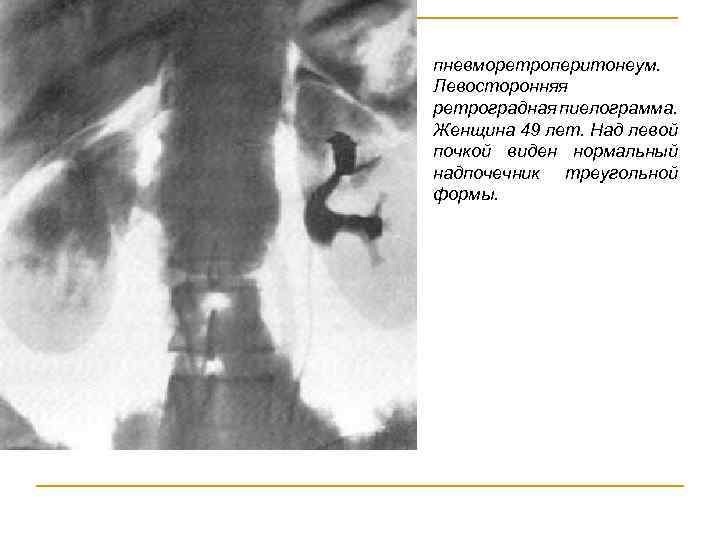

Пневморетроперитонеумом Введение газа в рыхлую пресакральную клетчатку, которая связана с различными слоями ретроперитонеального пространства. Этот метод дает возможность исследовать рентгенологически тазовые органы, опухоли и кисты в малом тазу, почки, надпочечники, забрюшинные опухоли, поджелудочную железу, желчный пузырь, частично кишечник, а также средостение и органы грудной клетки.

пневморетроперитонеум. Левосторонняя ретроградная пиелограмма. Женщина 49 лет. Над левой почкой виден нормальный надпочечник треугольной формы.